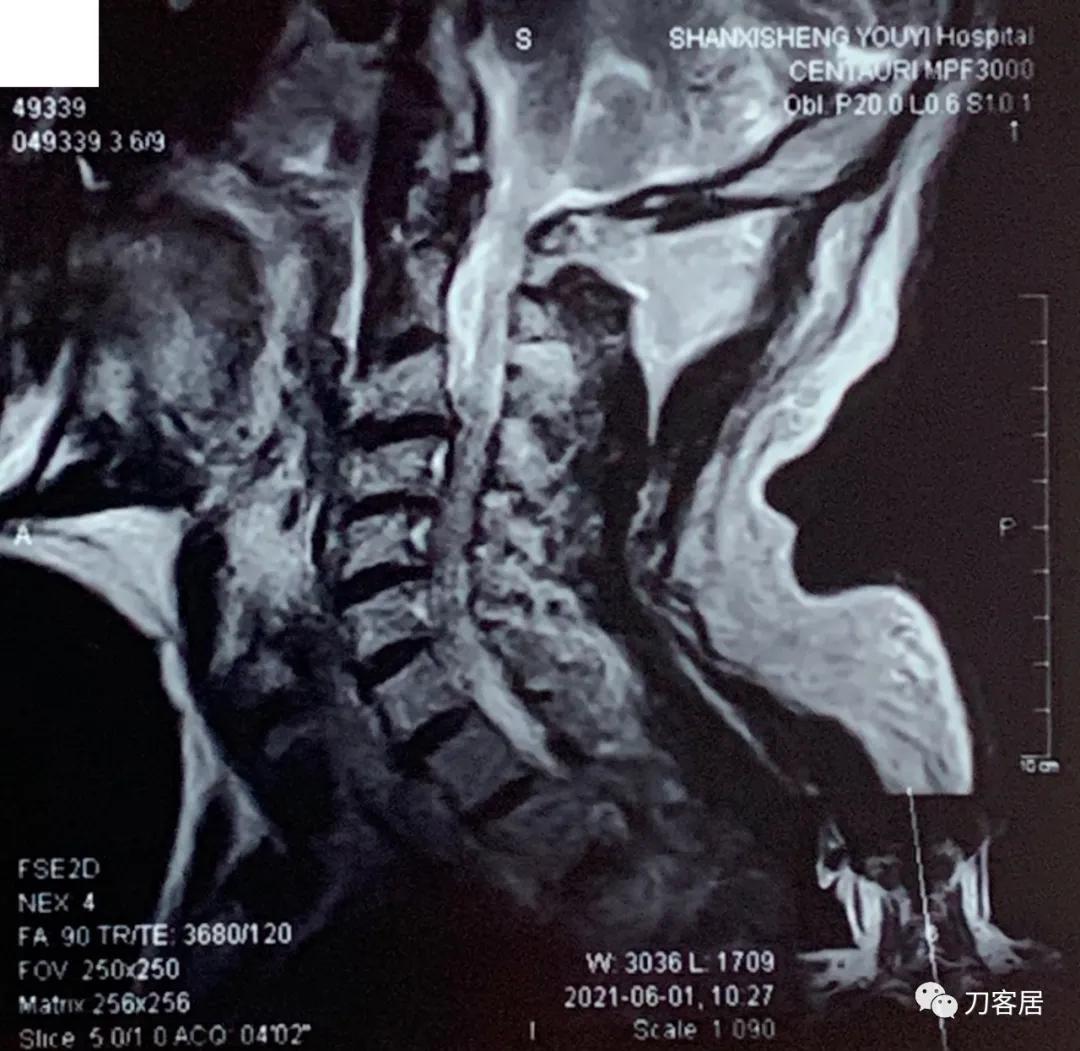

2021年6月1日外院的颈椎MRI

自带颈椎MRI提示颈3-4,颈4-5,颈5-6,颈6-7椎间盘突出,椎管狭窄。目前无明确上位神经损伤表现,暂不处理。骨密度提示骨量减少,但因患者的临床表现,符合骨质疏松症的表现,夜间痛明显,活动后缓解,且已高龄,虽然患者的颈椎MRI片子显示多节段椎间盘突出,椎管狭窄,比较严重, 但无明确的神经损伤表现,病理反射阴性,所以,选择保守治疗,先行抗骨质疏松,以观疗效后决定是否在未来需要手术治疗。

诊断: 骨质疏松症,颈3-7椎间盘突出,颈椎管狭窄。